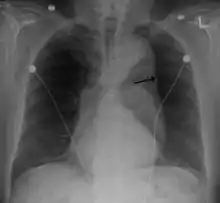

A thoracic aortic aneurysm is an aortic aneurysm that presents primarily in the thorax.

A thoracic aortic aneurysm is the "ballooning" of the upper aspect of the aorta, above the diaphragm. Untreated or unrecognized they can be fatal due to dissection or "popping" of the aneurysm leading to nearly instant death. Thoracic aneurysms are less common than an abdominal aortic aneurysm.[2] However, a syphilitic aneurysm is more likely to be a thoracic aortic aneurysm than an abdominal aortic aneurysm. This condition is commonly treated via a specialized multidisciplinary approach with both vascular surgeons and cardiac surgeons.